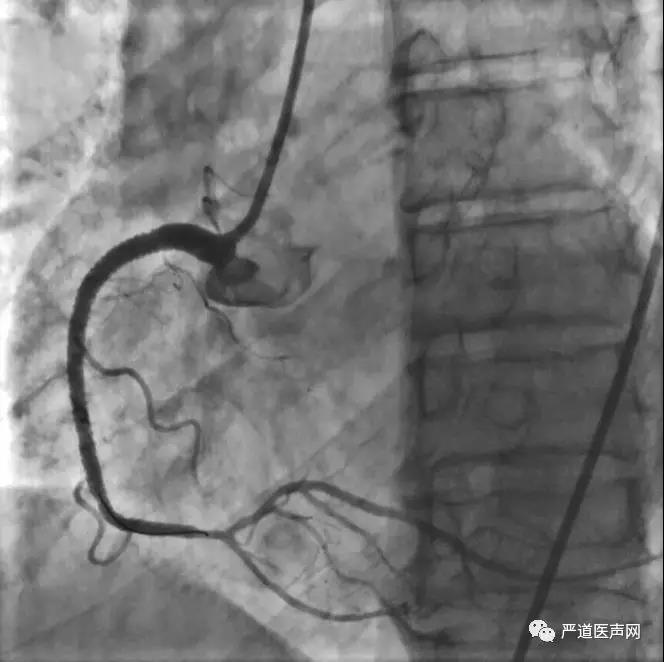

张瑞环教授给我们带来了一例右冠CTO的典型病例:患者为71岁男性,入院诊断为冠心病/缺血性心肌病、慢性心衰(NYHA III级)、心律失常 室早、高脂血症、高尿酸血症。

第一次造影显示:右冠分出锐缘支后即闭塞;前降支中端为弥漫性病变。术中右冠未做特殊处理,前降支给予支架植入达到完全开通。患者术后50天复查,劳力性胸闷症状较前减轻,实验室检查结果较前好转,第二次冠脉造影提示:右冠情况同前,左冠管柱尚可。

分析患者病情,患者虽症状较前改善,但心功能指标仍然偏低,开通右冠对患者心功能改善有益。鉴于右冠之前有介入治疗史,并且表现为两处较长病变、侧支循环尚可,所以选择逆向造影方案。通过左冠的侧支循环进入右冠远端进行逆行性造影,并根据造影结果于右冠远端植入3枚支架,术后造影如下图所示:

张瑞环教授最后总结了CHIP患者的治疗策略,指出此类患者PCI术中应有可靠地血流动力学证据支持,冠脉内影像可以优化手术效果,同时术后合理的药物治疗方案对改善预后也起着重要作用。